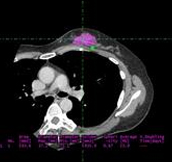

3D volume rendering reconstruction for separation of different soft tissues.

Tumor volume calculation in soft tissue.